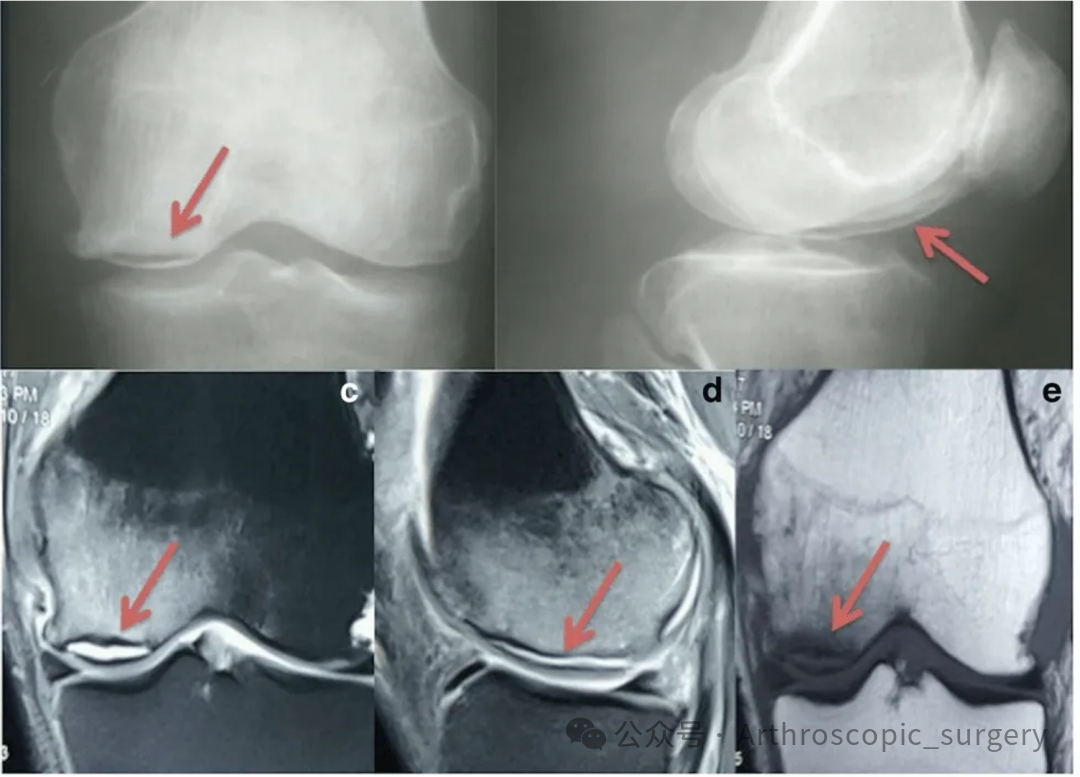

内侧半月板外突是MRI诊断MMRTs可靠且有用的征象。

推荐意见 17:

“鬼影征(Ghost sign)”是MRI诊断MMRTs可靠且有用的征象。

推荐意见 18:

“截断征”(多见于冠状位MRI)是MRI诊断MMRTs可靠且有用的征象。

推荐意见 19:

内侧半月板根部附着处(胫骨平台后内侧)的骨髓水肿,可作为MRI诊断MMRTs的参考征象。